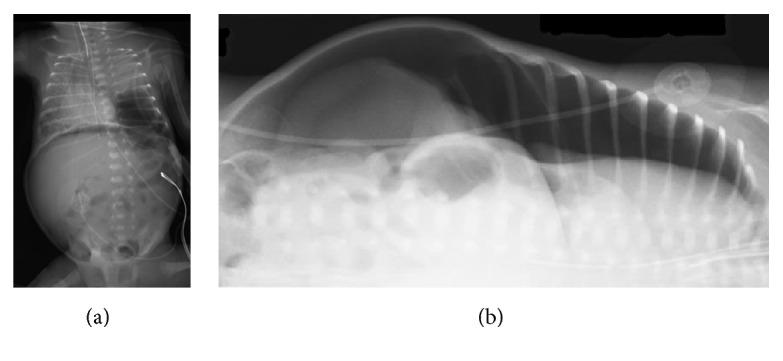

Pneumoperitoneum in a preterm neonate usually indicates perforation of the intestine and is considered a surgical emergency. However, there are cases of pneumoperitoneum with no evidence of rupture of the intestine reported in the literature. We report a case of pneumoperitoneum with no intestinal perforation in a preterm neonate with respiratory distress syndrome who was on high frequency oscillatory ventilation (HFOV). He developed bilateral pulmonary interstitial emphysema with localized cystic lesion, likely localized pulmonary interstitial emphysema, and recurrent pneumothoraces. He was treated with dexamethasone to wean from the ventilator. Pneumoperitoneum developed in association with left sided pneumothorax following mechanical ventilation and cardiopulmonary resuscitation. Pneumoperitoneum resolved after the pneumothorax was resolved with chest tube drainage. He died from acute cardiorespiratory failure. At autopsy, there was no evidence of intestinal perforation. This case highlights the fact that pneumoperitoneum can develop secondary to pneumothorax and does not always indicate intestinal perforation or require exploratory laparotomy.

摘要